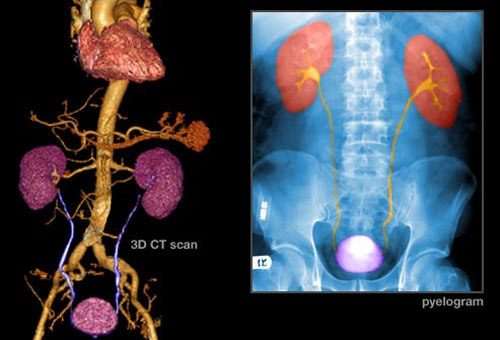

Phương pháp xác định ung thư bàng quang

Nếu bạn có nguy cơ cao bị ung thư bàng quang hoặc có nhiều triệu chứng khả nghi bệnh như trê, các bác sĩ sẽ yêu cầu bạn làm xét nghiệm nước tiểu. Nếu cần thiết, bác sĩ sẽ tiến hàng nội soi bàng quang để thấy cụ thể bên trong bàng quang. Kiểm tra sinh thiết là cách tốt nhất để chẩn đoán ung thư và nó được thực hiện khi các biện pháp trên không cho kết quả rõ ràng.

Chụp cắt lớp cũng là một biện pháp xác định ung thư bàng quang